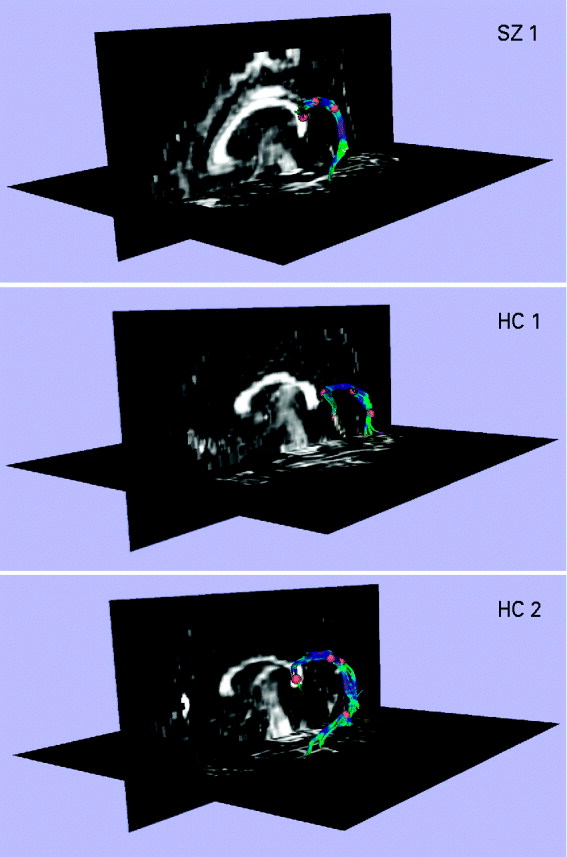

Extraction of the arcuate fasciculus

Fig. 1. Extracting the left arcuate fasciculus from participants' diffusion tensor (DT) images with deterministic (streamline) tractography. The extracted arcuates of three representative participants, one patient with schizophrenia (SZ) and two healthy controls (HCs), are shown overlaid onto a sagittal and axial slice of their fractional anisotropy (FA) image. The first step in the tractography procedure involved manually placing a cubic region of interest (i.e. a fiducial) of side 3.5 mm in the dorsal longitudinal fibers of the arcuate fasciculus, according to the protocol of Catani et al. (Reference Catani and Thiebaut de Schotten2008). The voxels defined by this fiducial were then used as seedpoints for deterministic (streamline) tractography, which followed the direction defined by the principal eigenvector. A step size of 1.5 mm was used, and tractography was terminated upon reaching a voxel of FA <0.25 (the stopping criterion). The small number of voxels defined by the fiducial meant that immediate feedback was available as to the legitimacy of the fiducial's location. The spatial position of the fiducial was then adjusted until the distinctive ventrally projecting, curved fibers of the arcuate fasciculus became apparent. Additional fiducials (typically between 1 and 3) were then placed along the length of the arcuate to augment the fiber bundle. The fiducials for all participants were placed by a single rater who was blind to subject diagnosis.